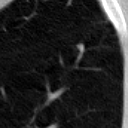

The current study focuses on lung nodule retrieval from a database of CT scans, where patches taken from CT slices of pulmonary nodules are to be mapped into an embedding. LIDC-IDRI [5] is a dataset of thoracic CT scans of 1,010 patients. All the scans were annotated by up to four radiologists, where each one identified, segmented and evaluated separately the lung nodules of a diameter above . Their evaluation also included ratings for a set of 9 characteristics: Subtlety, Internal structure, Calcification, Sphericity, Margin, Lobulation, Spiculation, Texture and Malignancy. The rating system was based on a discrete score of 1-5. Four examples of nodule patches are illustrated in Figure 2: 2 benign (a, b) and 2 malignant (c, d). A rounded vector of the mean rating is bellow each nodule, with the characteristics ordered according to the listing above. The most prominent difference between a and b is the calcification: 3 (solid) and 6 (absent) accordingly. d compared to c has a more defined margin, is more lobulated, but less spiculated. The malignancy score is used to define malignancy classes: score of 1-2 is benign, score of 3 is unknown, and a score of 4-5 is malignant.

(a) Benign

3, 1, 3, 3, 4, 3, 1, 5, 1

(b) Benign

3, 1, 6, 5, 5, 1, 1, 5, 2

(c) Malignant

5, 1, 6, 3, 3, 4, 1, 5, 5

(d) Malignant

4, 1, 6, 3, 4, 2, 2, 5, 4